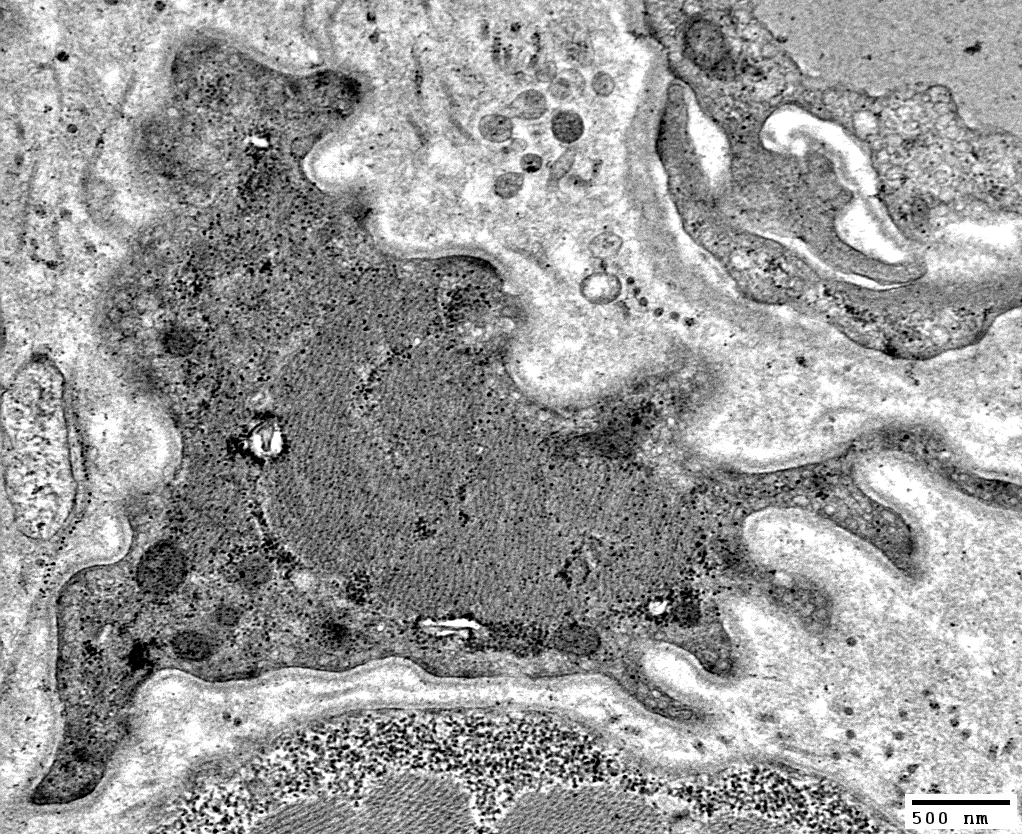

Atrophic Muscle fibers: Ultrastructure

Atrophic Muscle Fibers: General Features

- Size: Small

- Internal architecture

- Muscle fiber surface

- Basal lamina: May project empty sleeves or redundant loops from fiber surface

- May be smooth or undulating

Muscle Fiber Atrophy: Sarcolemma

Atrophic Muscle Fibers

Undulating Basal lamina & Sarcolemma

Basal Lamina: Redundant